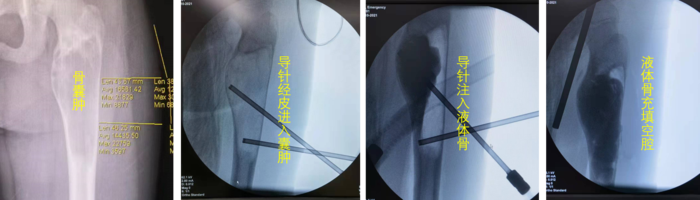

为了减少手术后的复发,避免小舞蹈家以后发生骨折,我们改良了传统的激素注射的方法 ,在手术中用了硬化剂以及各种新设计的器械破坏囊肿环境,反复冲洗后注射液体骨,手术很顺利。